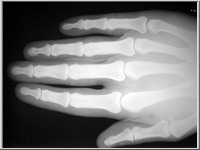

A képekre kattintva a röntgenfelvételek üveglemezeinek reprodukcióit, a kis képek jobb felső sarka melletti ikonokra klikkelve pedig az üveglemezeket védő, Gothard által feliratozott, a felvételek adatait tartalmazó borítékok reprodukcióit láthatjuk.

Az 1. sorszámú lemez elveszett, csak papírmásolat maradt fenn róla. A 25. és 26. sorszámú borítékok 2-2 felvételt tartalmaznak (itt a-val és b-vel jelölve), míg a 32. sorszámú lemez eltört, két darabban van.